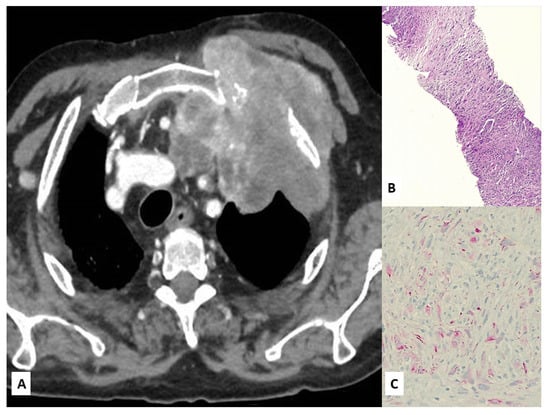

3. Unusual Radiological Presentation

- Rossi, G.; Caroli, G.; Caruso, D.; Stella, F.; Davoli, F. Pseudocarcinomatous Mesothelioma: A Hitherto Unreported Presentation closely simulating primary lung cancer. Int. J. Surg. Pathol. 2021, 24. [Google Scholar] [CrossRef]

- Larsen, B.T.; Klein, J.R.; Hornychová, H.; Nuti, R.; Thirumala, S.; Leslie, K.O.; Colby, T.V.; Tazelaar, H.D. Diffuse intrapulmonary ma-lignant mesothelioma masquerading as interstitial lung disease: A distinctive variant of mesothelioma. Am. J. Surg. Pathol. 2013, 37, 1555–1564. [Google Scholar] [CrossRef]

- Lacle, M.M.; Van Oosterhout, M.F. An Unusual Presentation of Malignant Pleural Mesothelioma. J. Thorac. Oncol. 2013, 8, e63–e64. [Google Scholar] [CrossRef]

- Rossi, G.; Cavazza, A.; Turrini, E.; Costantini, M.; Casali, C.; Morandi, U.; Dallari, R. Exclusive Intrapulmonary Lepidic Growth of a Malignant Pleural Mesothelioma Presenting with Pneumothorax and Involving the Peritoneum. Int. J. Surg. Pathol. 2006, 14, 234–237. [Google Scholar] [CrossRef]

- Lococo, F.; Marchesini, G.; Taddei, S.; Rapicetta, C. An insidious cause of spontaneous pneumothorax in an elderly woman. Eur. J. Cardio Thoracic Surg. 2015, 49, e63–e64. [Google Scholar] [CrossRef] [PubMed][Green Version]

- Hassan, I.; Goolam-Mahomed, A. An unusual cause of an anterior mediastinal mass. Respir. Med. Case Rep. 2014, 12, 52–54. [Google Scholar] [CrossRef]